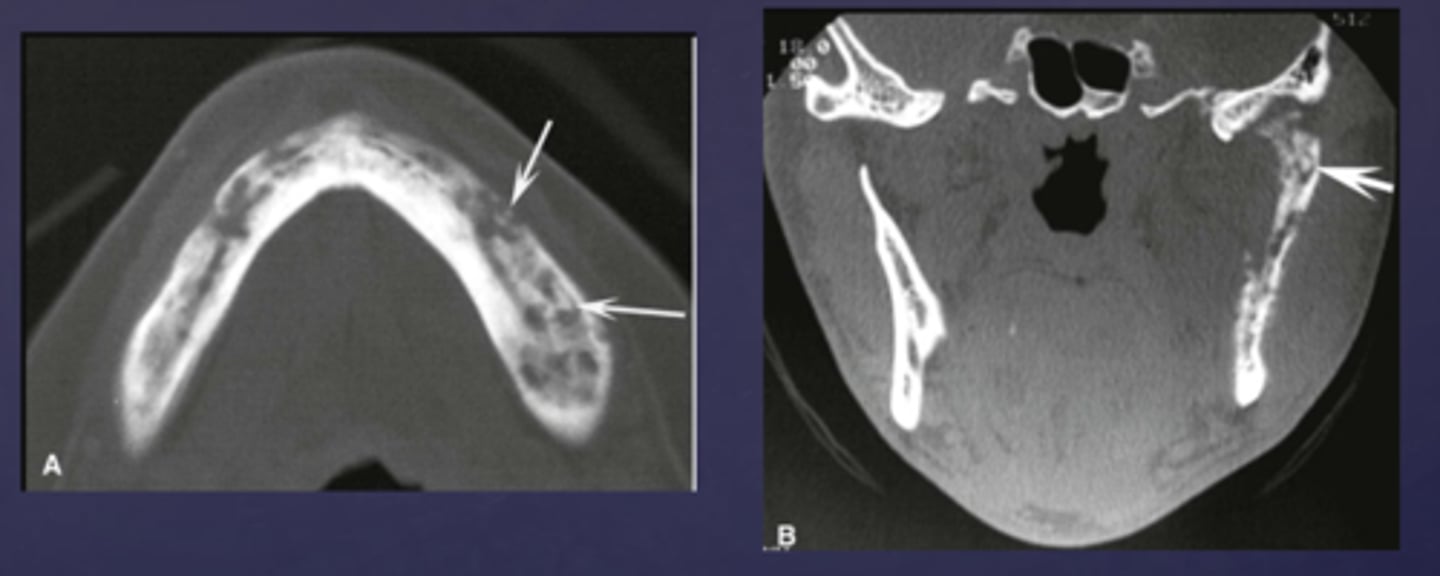

What type of osteomyelitis? Radiographic features :

- No radiographic manifestation in early stages

- Imaging features vary depending on the stage of disease

acute osteomyelitis

What phase of osteomyelitis?

(periphery: poorly defined, non-corticated, gradual transition to normal trabeculae)

- Decrease in density of bone, loss of sharpness of trabeculae

- Localized or scattered regions of radiolucency, ill defined periphery

acute osteomyelitis (internal structure)